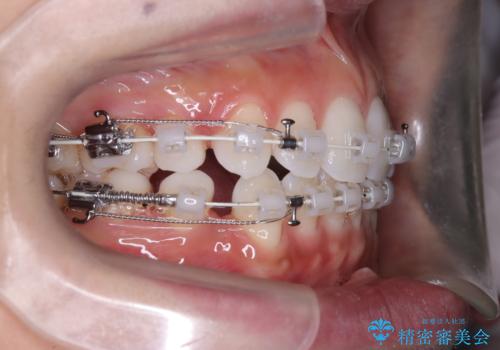

歯並びと横顔のバランスを整えるためには、前歯を後方に移動させるスペースの確保が必要です。そのため、上下左右の第一小臼歯(合計4本)を抜歯し、ワイヤー矯正で前歯の突出感と叢生(がたつき)を同時に改善する治療計画を立てました。歯を抜くことに抵抗がある方も多いですが、口元の印象を変えるためには非常に効果的な方法です。

上下左右の小臼歯を抜歯後、ワイヤー矯正装置を装着し、全体のバランスを見ながら歯を移動させていきました。特に前歯の後方移動では、抜歯スペースを活かして口元を内側に下げることに重点を置きました。また、八重歯も時間をかけて丁寧に整列させ、左右の正中(真ん中の位置)もぴったりと揃えることができました。